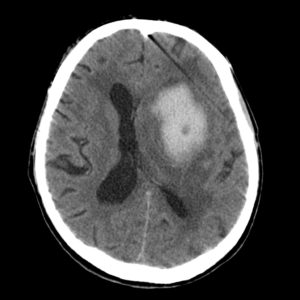

Компьютерная томография (КТ) и магнитно-резонансная томография (МРТ) — наиболее важные диагностические исследования при инсульте. КТ в большинстве случаев позволяет чётко отдифференцировать «свежее» кровоизлияние в мозг от других типов инсультов, МРТ предпочтительнее для выявления участков ишемии, оценки распространённости ишемического повреждения.

КТ при геморрагическом инсульте

Думаю, разница понятна. Особенно для начинающих. Все просто: Геморрагический - светлое пятно. Ишемический - темное.